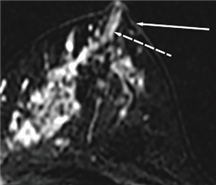

유방 MRI에서 관찰되는 '비종괴성 조영증강'은 암세포가 덩어리져 보이는 '종괴성 병변'과 다르게, 덩어리 없이 불규칙한 형태로 흩뿌려 놓은 것처럼 보이는 이미지를 말한다.

하지만 유두를 침범하거나 유두에서 근거리 내에 있는 암 병변은 유방 MRI 상 종괴성 병변보다는 흔히 비종괴성 조영증강의 형태로 보이는 경우가 많으나, 이에 대한 진단 정확도는 잘 알려지지 않았다.